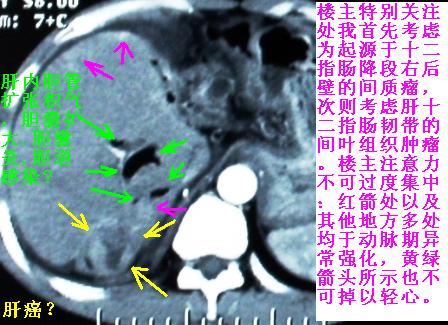

补充一点重要资料:今日查afp大于正常值10倍以上。因此,本病例最大可能应该是肝癌。

手术结果:

肝脏尾状叶肝癌(沿肝十二指肠韧带向下韧带内生长,门腔间隙外压增大),大结节性肝硬化,胆囊积脓,胆道感染。术中见肝外胆道2cm直径,肿瘤向前压迫胆管至扁平状态。

ct表现:1,胰腺钩突后方肿块,不均强化,中心密度低,钩突及门静脉前移。2:肝右后叶不均强化灶,突出肝表面,3:胆囊明显增大,肝内胆管及肝总管内积气。4:腹腔内少量积液。

胰头后方肿块,周边强化,胰头受压推移,肝脏右后叶异常强化灶,首先考虑肝癌后腹膜淋巴结转移;2、肝内胆管积气。